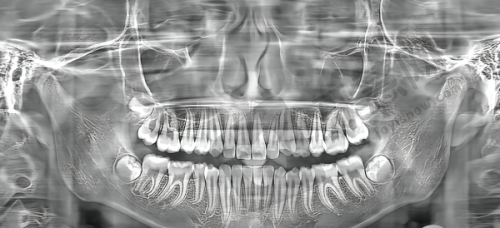

3. 设备精良:引进智能化全景X光机、3D口腔扫描仪等国内外可靠的口腔诊疗设备,提高了诊断的正确性,缩短了治疗时间,提升了患者的就诊体验。

深圳尚佳口腔门诊部是正规医院。它经深圳市宝安区卫生健康局审批成立,登记号为MADNA3RK - X44030617D1522。作为营利性医疗机构,诊疗范围涵盖多项口腔项目,且被列为深圳市定点单位,基础项目可报销。医院配备7张牙椅及数字化X光机、3D口扫仪等设备,严格执行“一人一机一消毒”的院感标准,手术室达层流要求。自2024年成立以来,保持稳定运营,无重大违规记录,并通过卫健委定期校验,管理规范。

深圳尚佳口腔门诊部成立于2024年,是经深圳市宝安区卫生健康局审批成立的正规口腔医疗机构。诊疗项目涵盖种植牙、正畸、儿童齿科等全项目。特色技术众多,如在种植牙上采用数字化技术,正畸结合数字化方案设计。其优势在于能为患者制定更科学合理的治疗方案。诊疗环境温馨舒适,候诊区宽敞明亮,诊室设计合理。医院配备智能化全景X光机、3D口腔扫描仪等精良设备。规模上,医院面积达1000平方米,设有7张牙椅。医生团队实力雄厚,像王冶医生从业近10年,完成超2000例种植手术;陈春美医生专注正畸领域,隐形矫正实例超500例。在患者中口碑良好,第三方平台评分高。